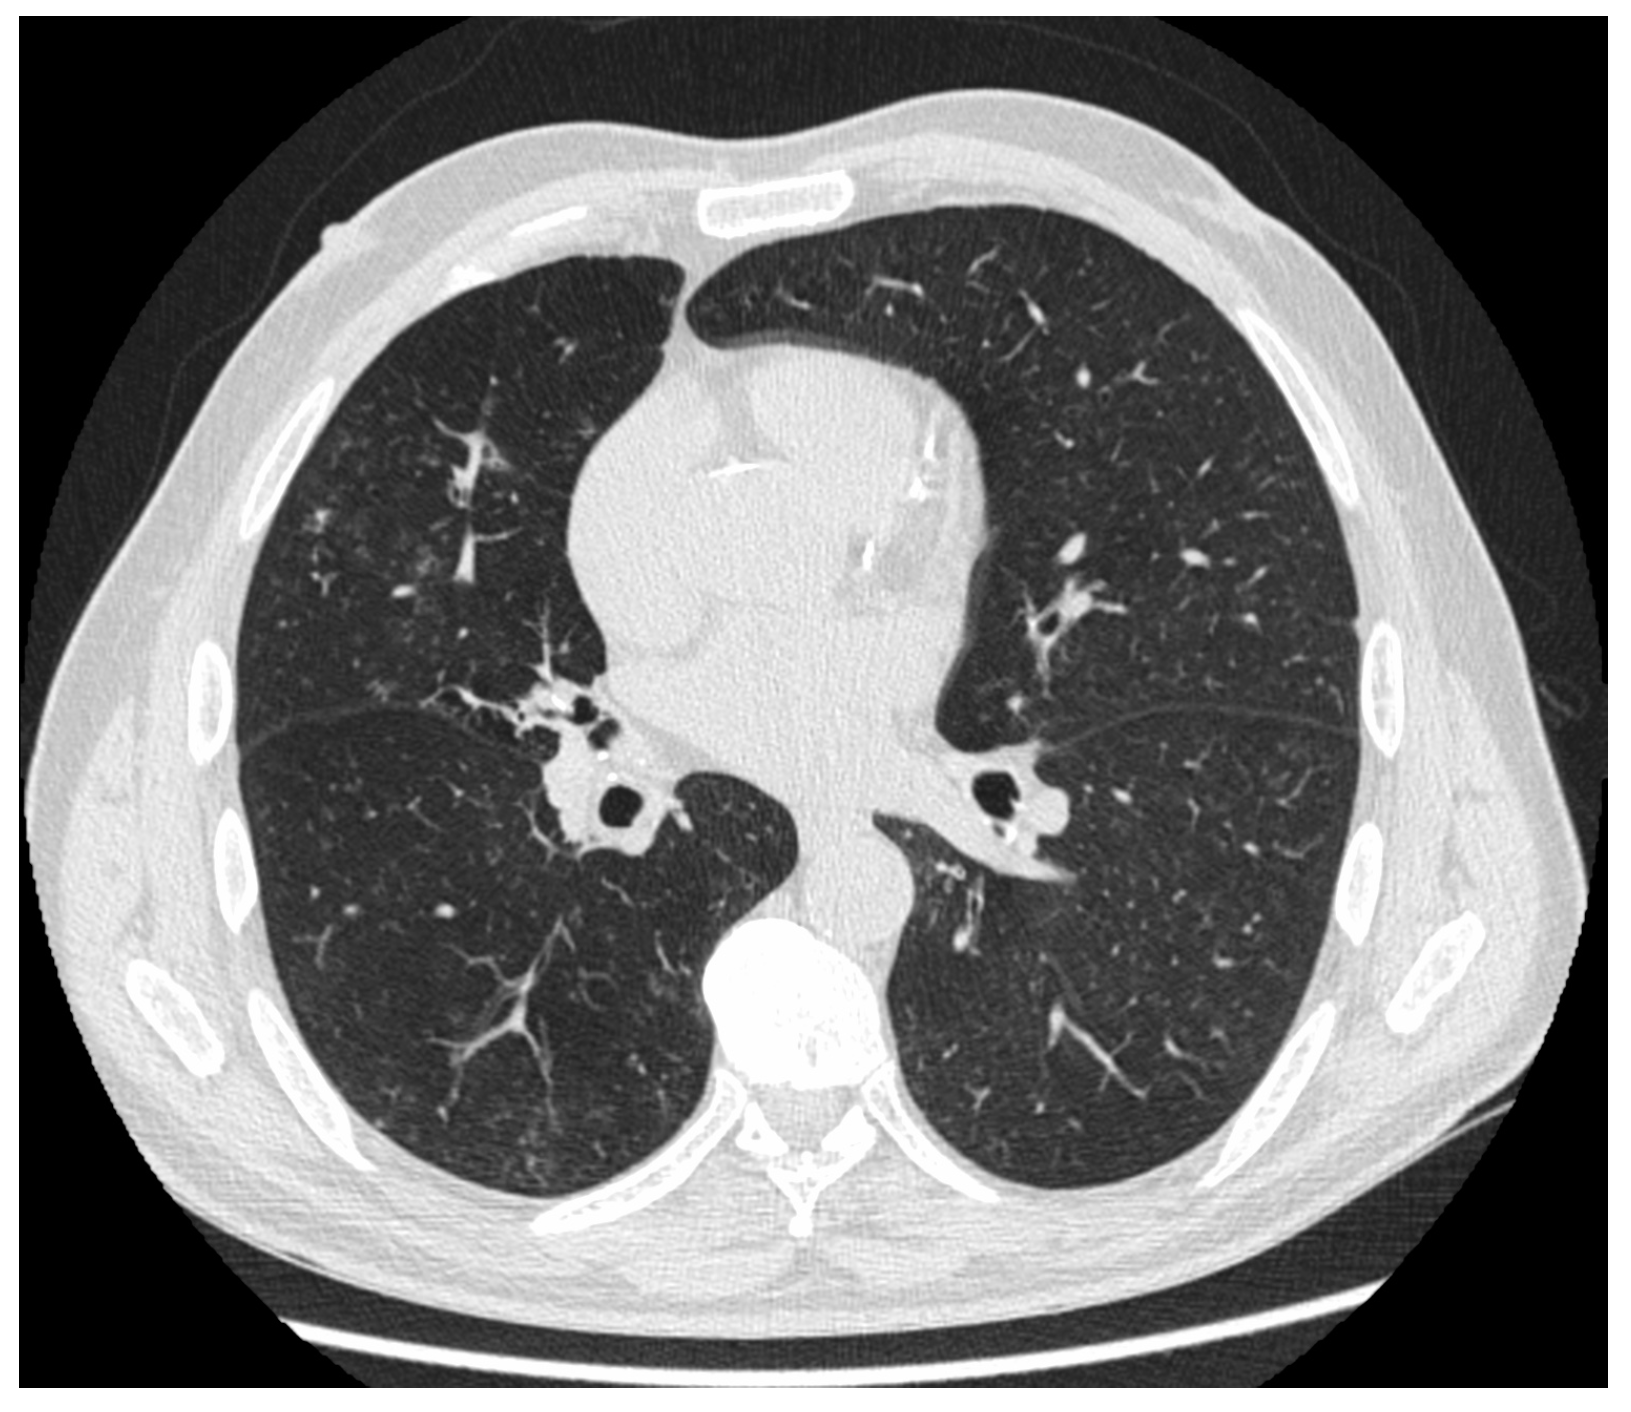

7. Pulmonary Langerhans Cell Histiocytosis

7.4. Diagnosis